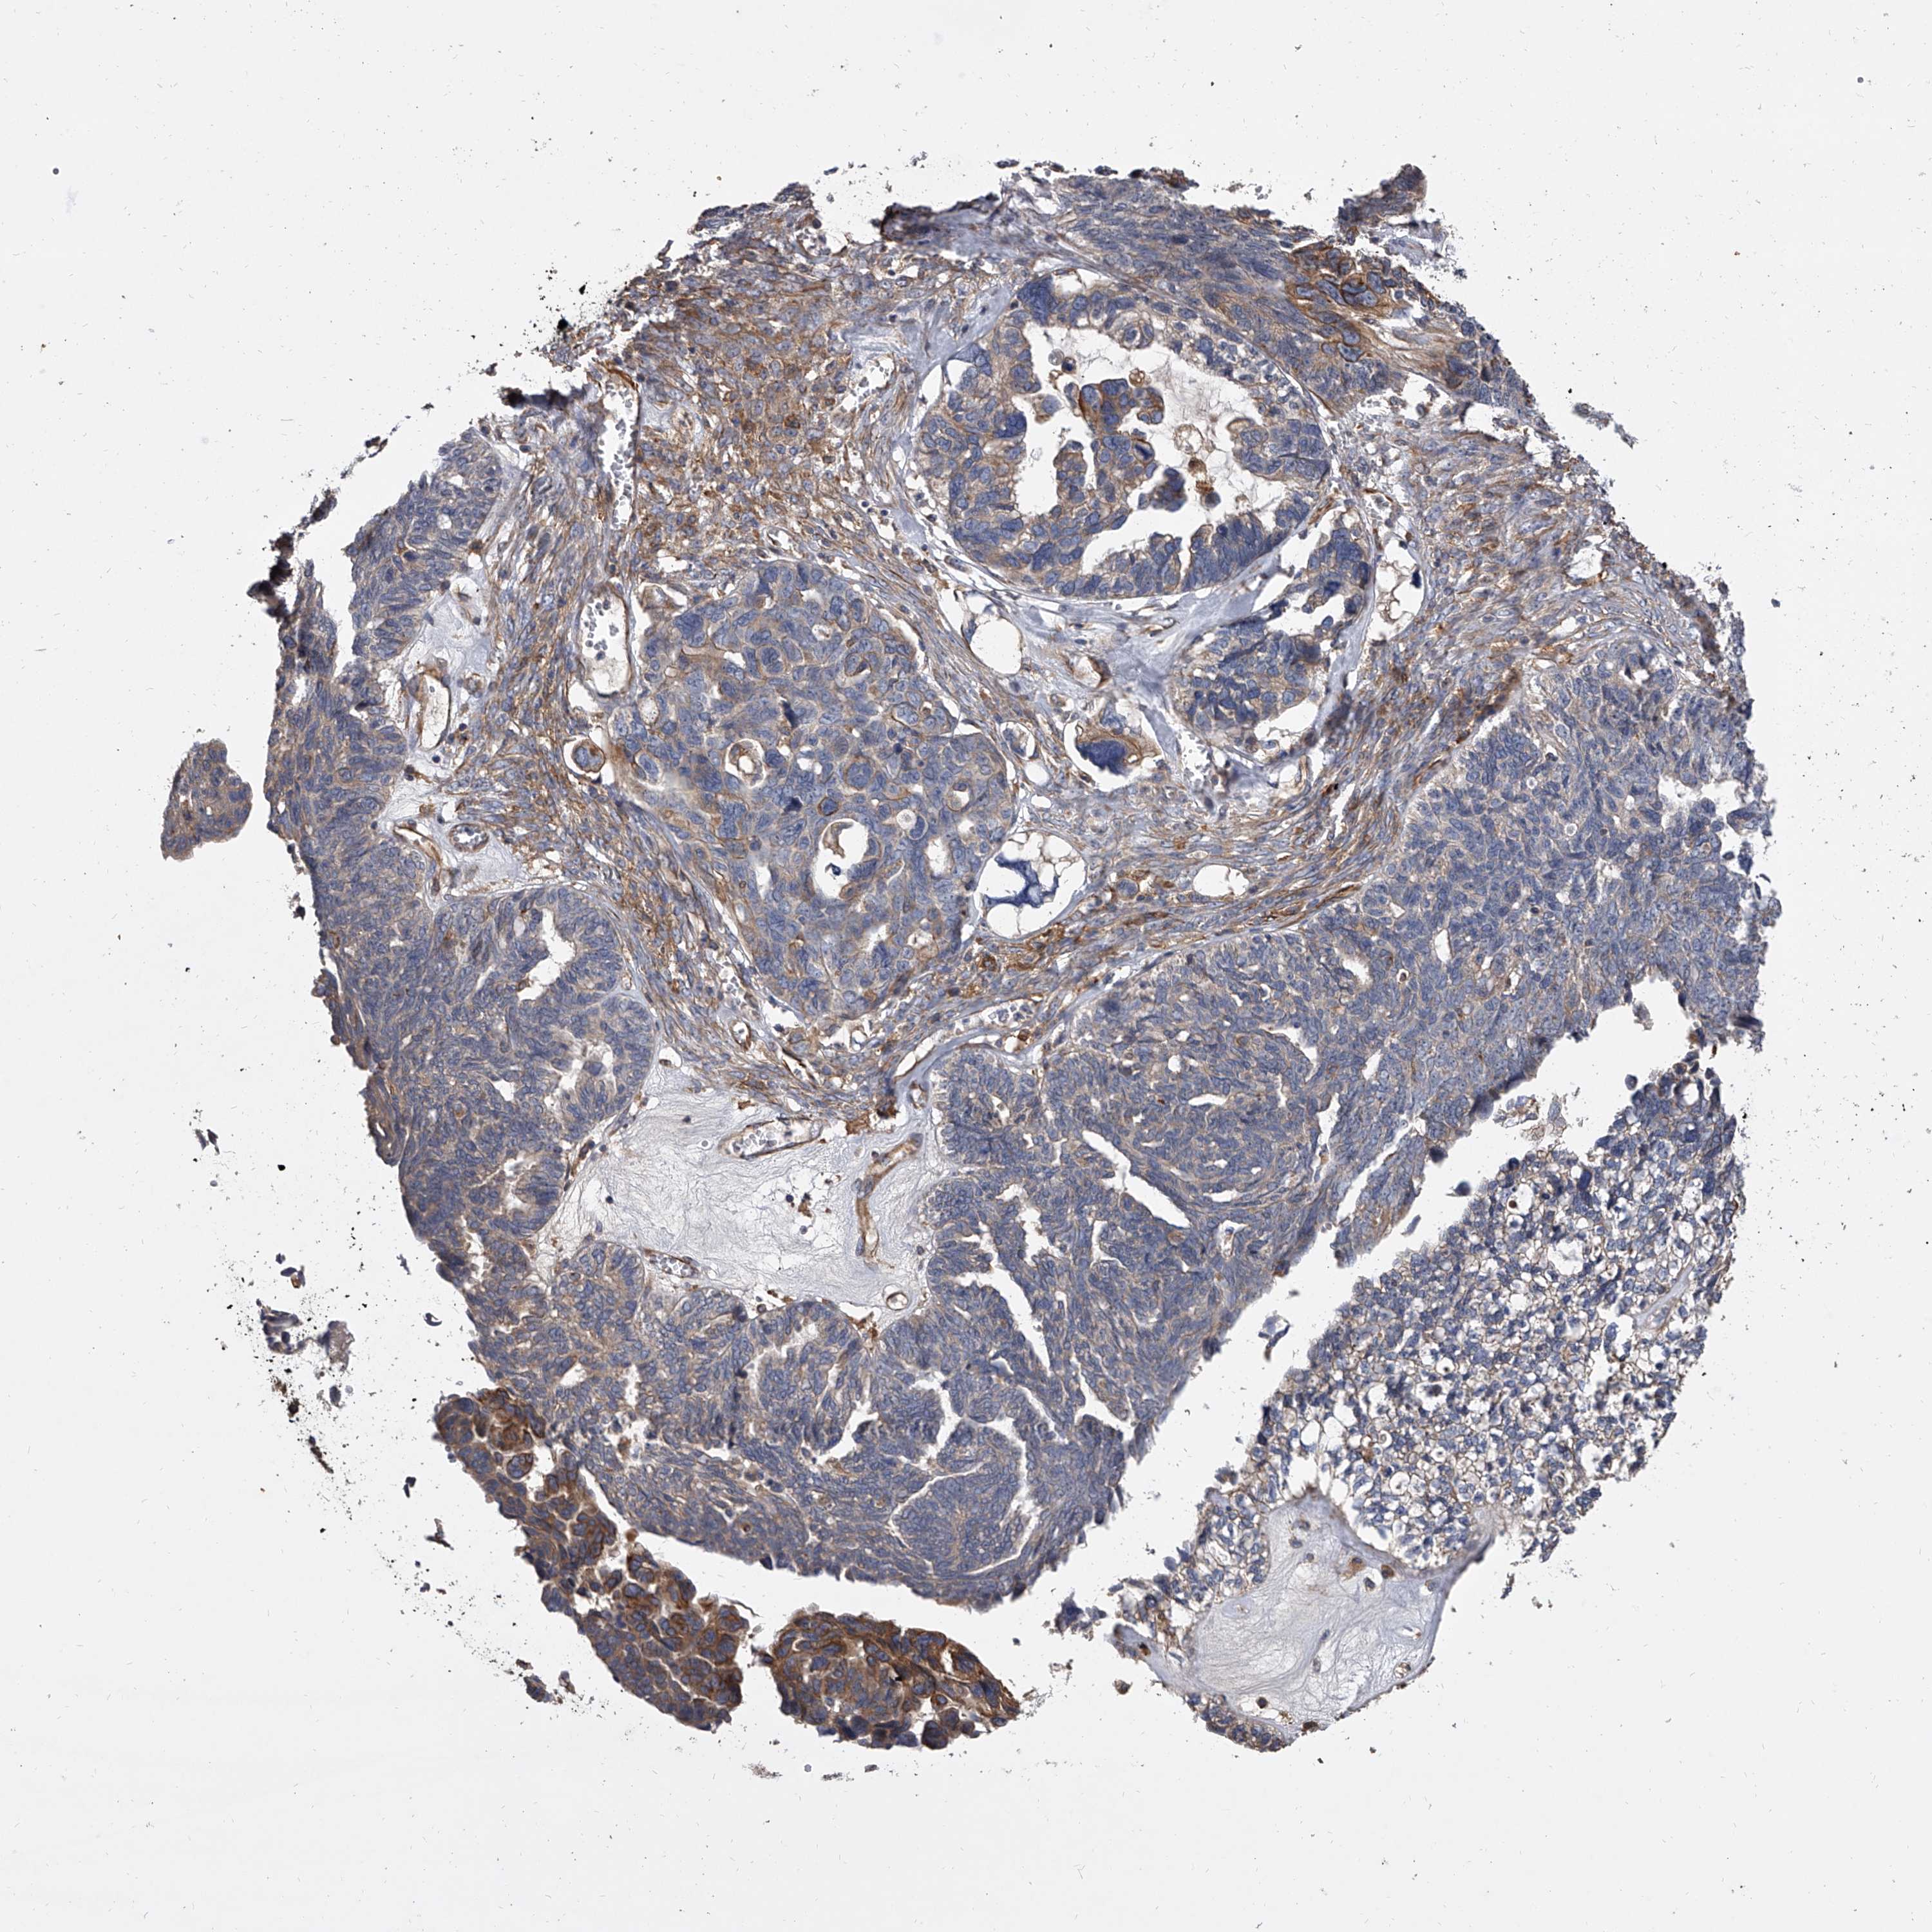

OVARIAN CANCER - Protein expressioni

A mouse-over function shows sample information and annotation data. Click on an image to view it in a full screen mode. Samples can be filtered based on level of antibody staining by selecting one or several of the following categories: high, medium, low and not detected. The assay and annotation is described here.

Note that samples used for immunohistochemistry by the Human Protein Atlas do not correspond to samples in the TCGA dataset.

Antibody stainingi

Antibody staining in the annotated cell types in the current human tissue is reported as not detected, low, medium, or high, based on conventional immunohistochemistry profiling in selected tissues. This score is based on the combination of the staining intensity and fraction of stained cells.

Each image is clickable and will lead to virtual microscopy that enables deeper exploration of all samples and also displays staining intensity scores, fraction scores and subcellular localization as well as patient and tissue information for each sample.

Antibody HPA031443

Staining

High

Medium

Low

Not detected

Intensity

Strong

Moderate

Weak

Negative

Quantity

>75%

75%-25%

<25%

None

Location

Nuclear

Cytoplasmic/membranous

Cytoplasmic/membranous,nuclear

Cystadenocarcinoma, serous, NOS

Carcinoma, endometroid

Cystadenocarcinoma, mucinous, NOS

Carcinoma, NOS